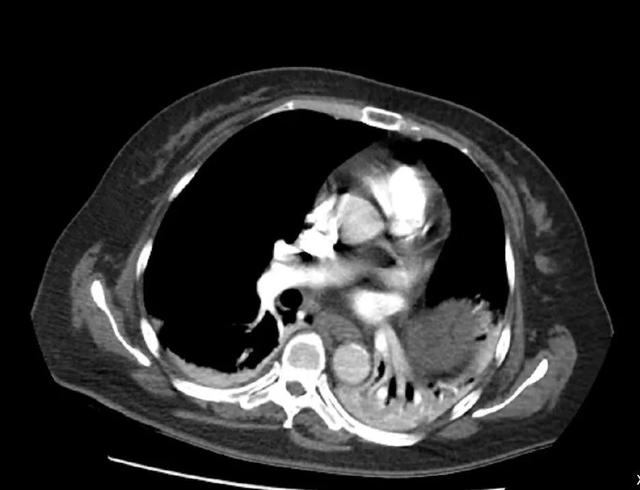

CT检查提示右肺下动脉栓塞,延伸到右肺动脉干

该病例的

复查随访

可见原有的大块血栓完全消失